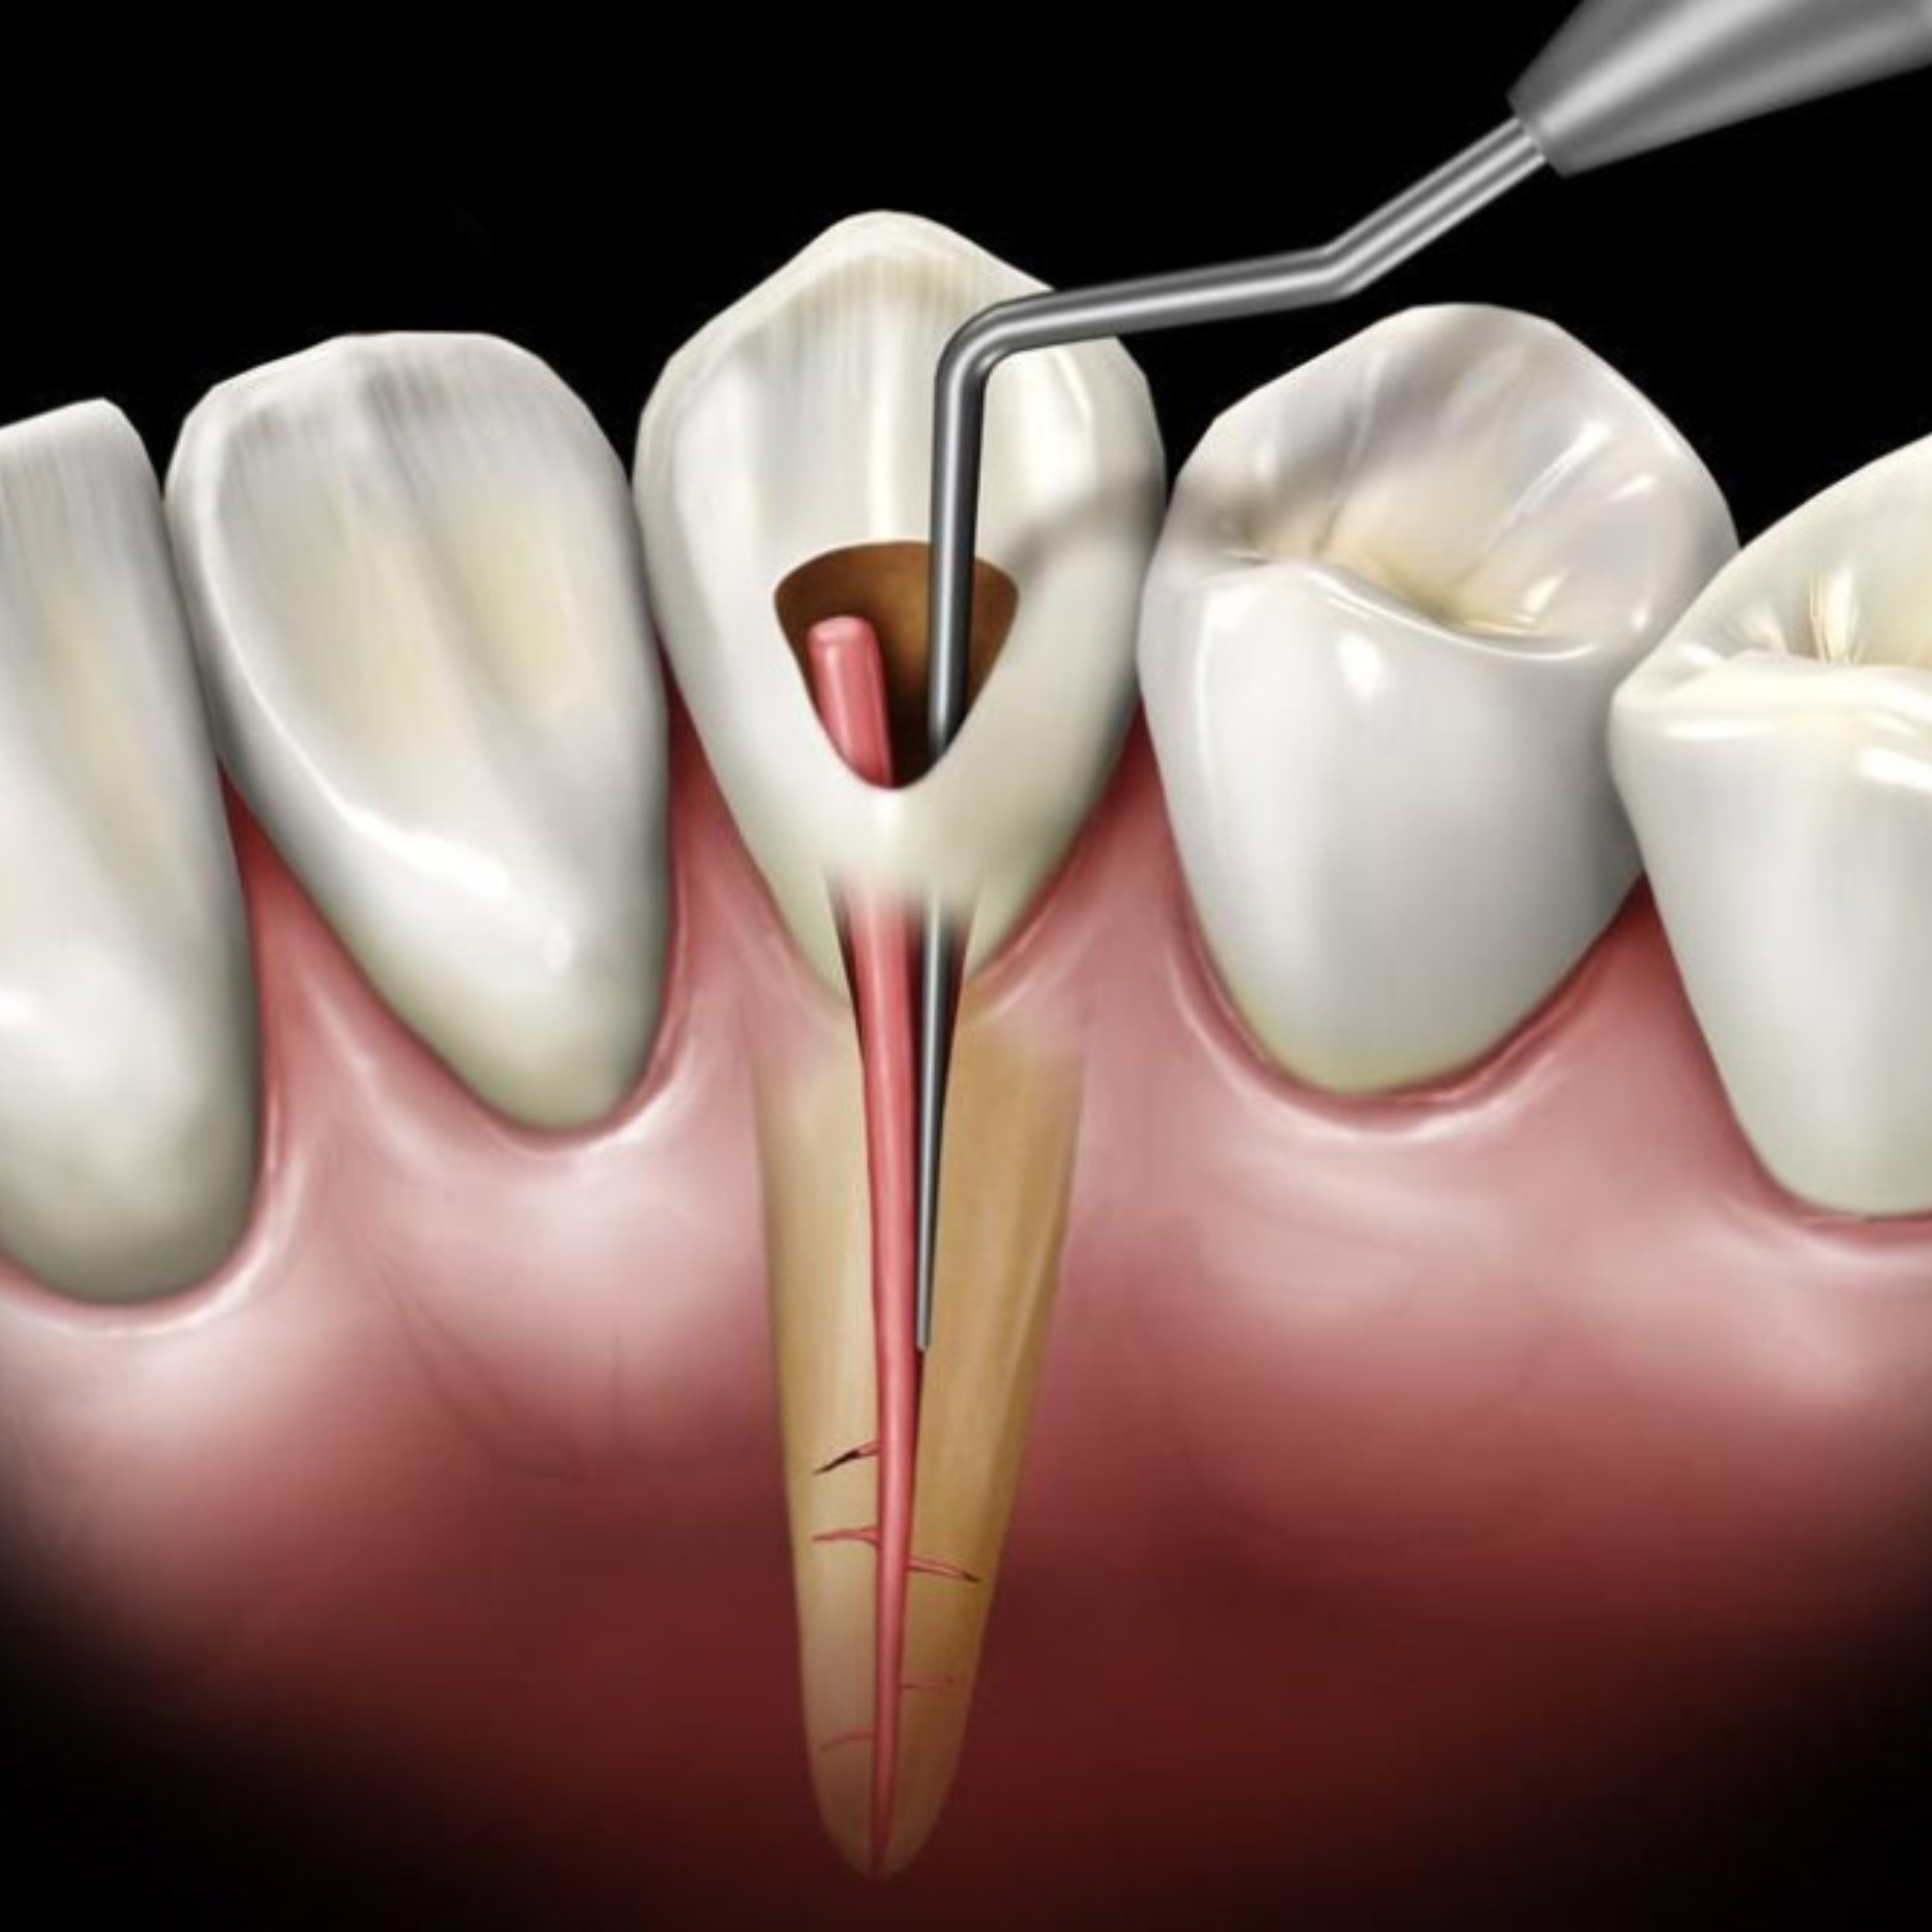

Lorsqu’une carie atteint la pulpe dentaire, un traitement endodontique (traitement de canal) est nécessaire.

Grâce à une technologie de microscopie et des instruments modernes, le Dr. Soumaya BenHamza nettoie et scelle le canal avec une précision exceptionnelle, permettant à votre dent de rester en place et de fonctionner normalement.